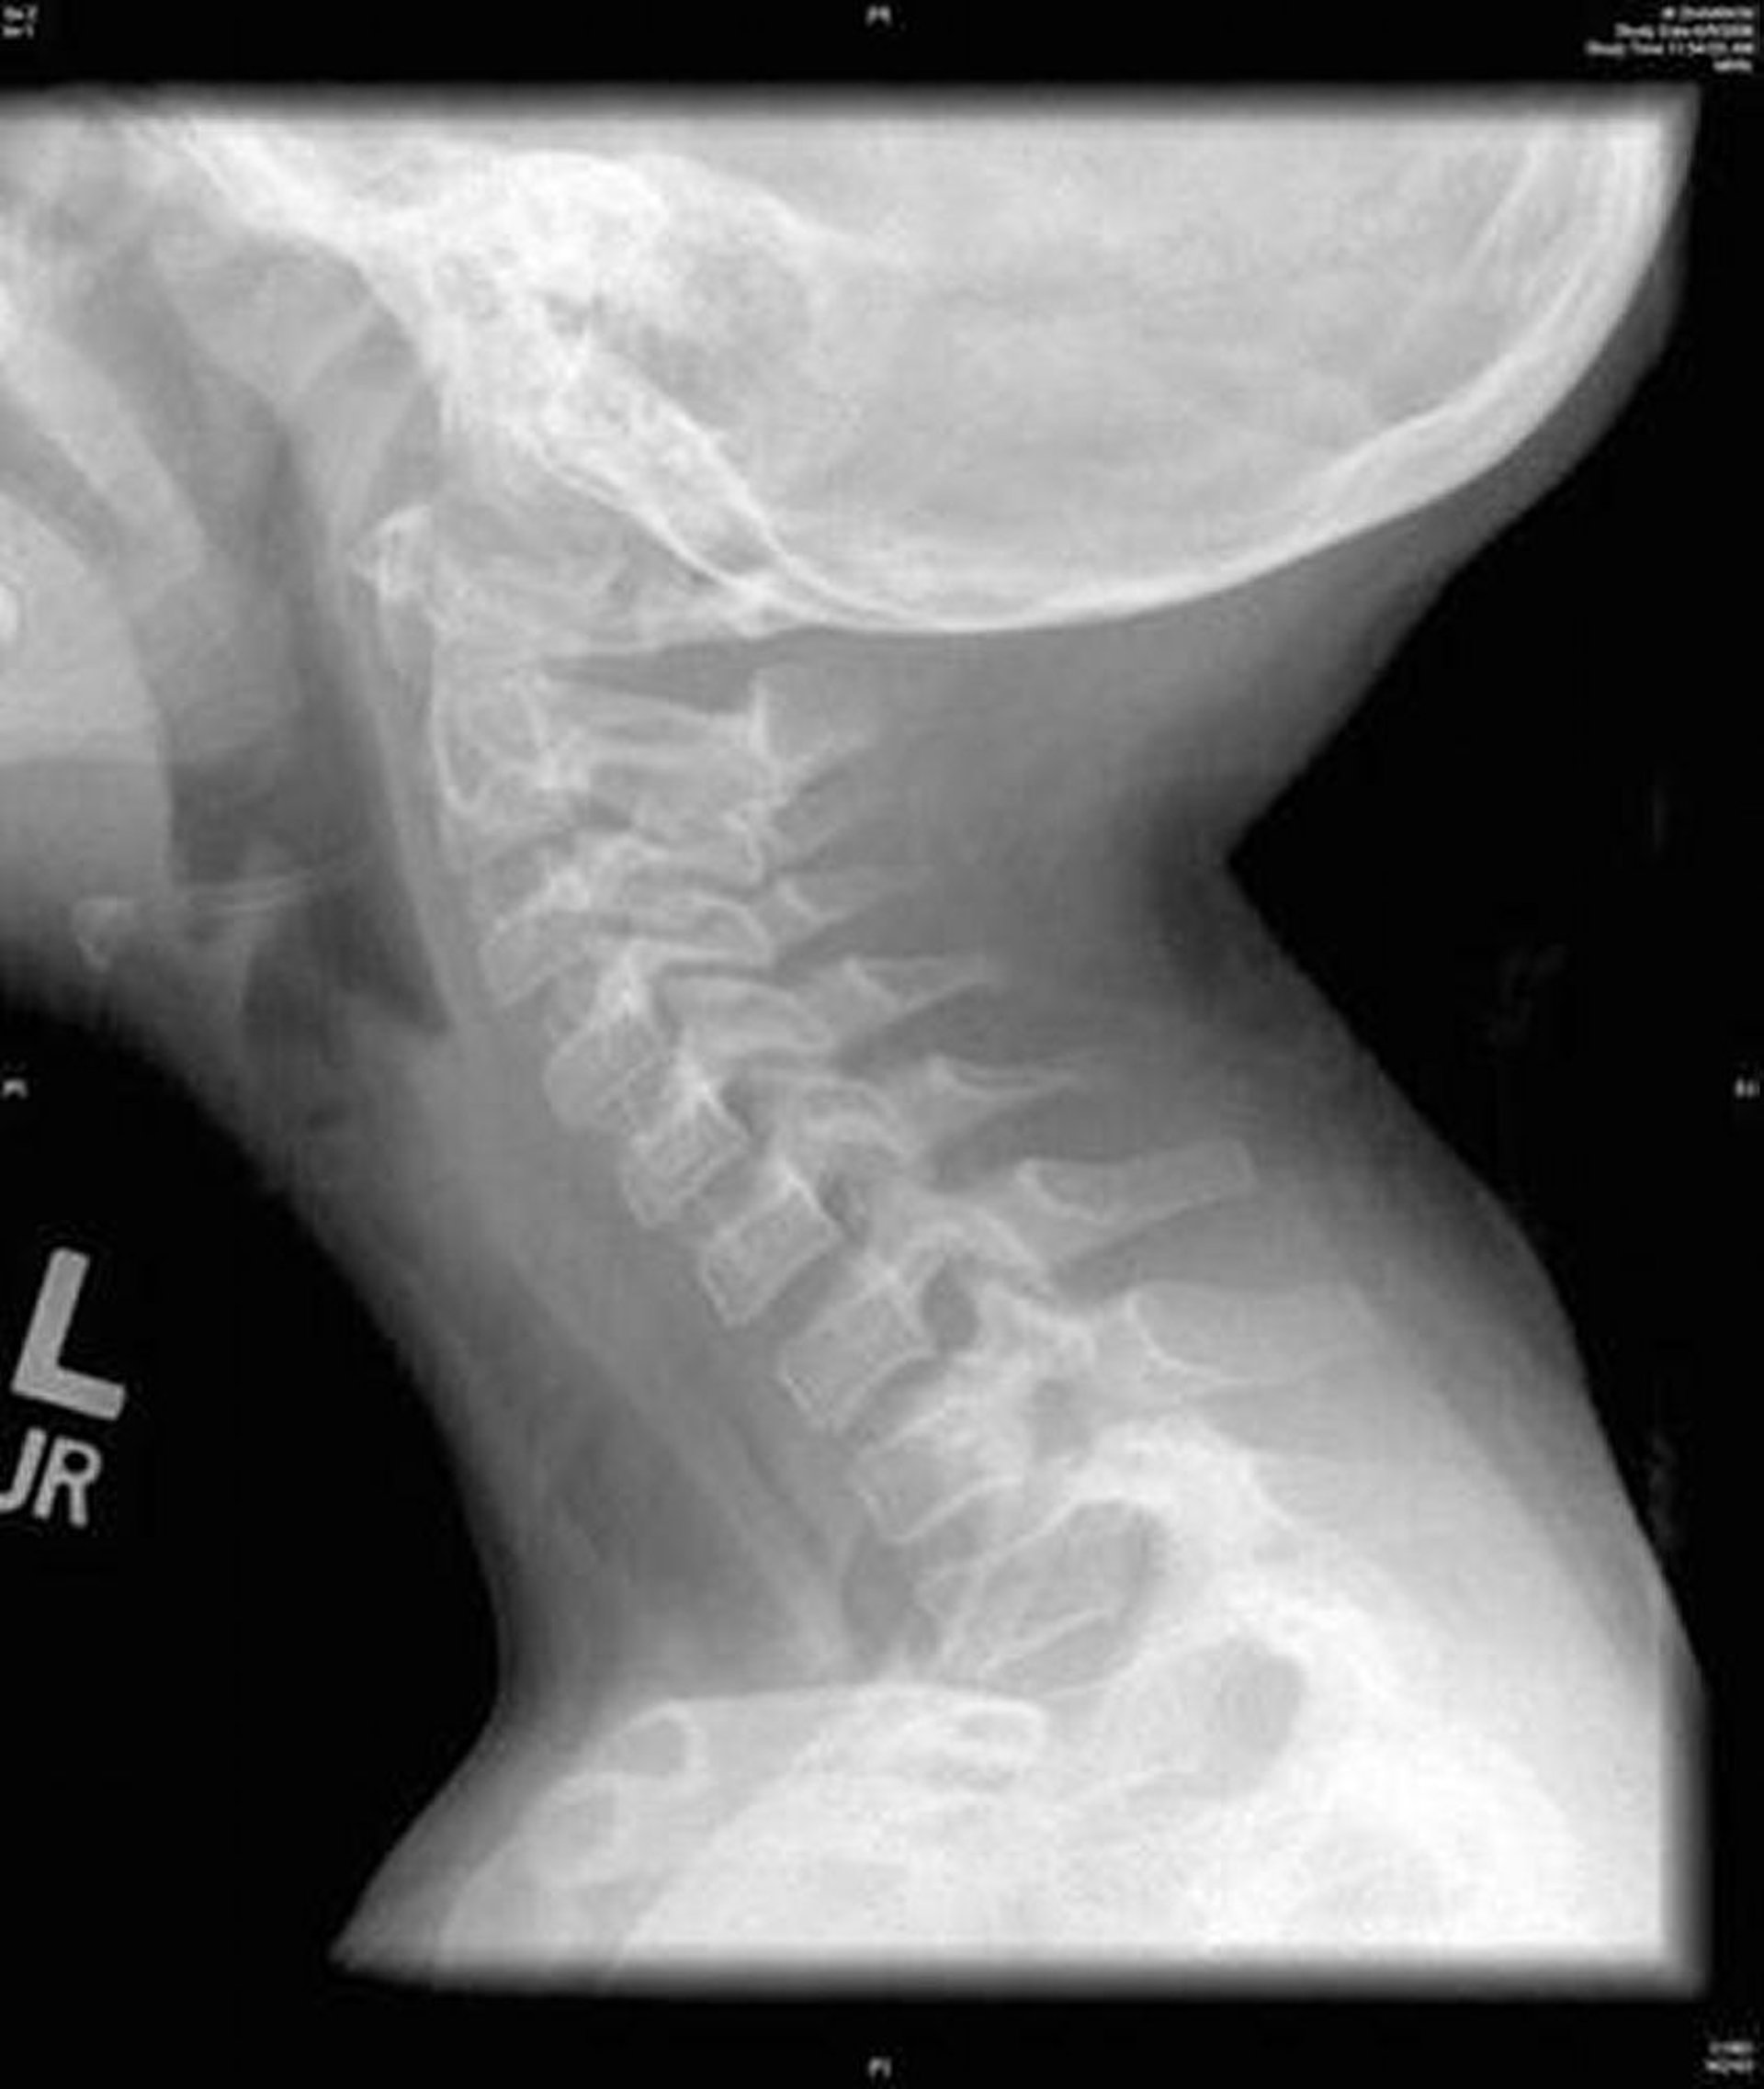

Бактериальный трахеит (рентгенограмма)

На этом изображении показана боковая рентгенограмма шеи, на которой видно диффузную неровность трахеи, характерную для бактериального трахеита.